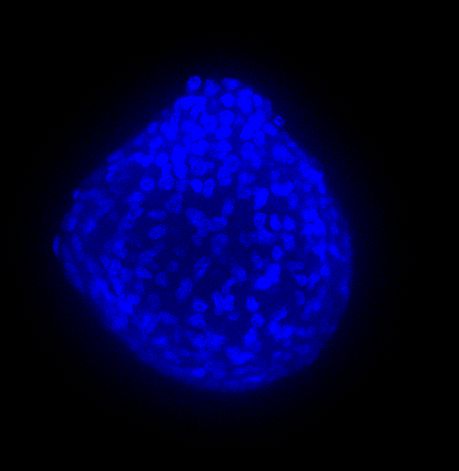

图 A:使用 20 倍空气物镜(顶部)和 25 倍硅油物镜(底部)获得的肿瘤球体 Z 堆栈的最大密度投影 (MIP)。活细胞用钙黄绿素(绿色)标记,死细胞用 PI(红色)标记。细胞核用 Hoechst(蓝色)染色。比例尺:100 um。这些图像是使用 CrestOptics X-Light V3 转盘获取的。

图 B:使用 20 倍空气物镜(左)和 25 倍硅胶物镜(右)获得的 3D 球体同一区域的放大。活细胞用钙黄绿素(绿色)标记,死细胞用 PI(红色)标记。细胞核用 Hoechst(蓝色)染色。这些图像是使用 CrestOptics X-Light V3 转盘获取的。

图 C:使用 20 倍空气物镜(左)和 25 倍硅油物镜(右)获得的球体的 3D 体积视图。活细胞用钙黄绿素(绿色)标记,死细胞用 PI(红色)标记。细胞核用 Hoechst(蓝色)染色。沿 Z 轴的比例尺:120 um。这些图像是使用 CrestOptics X-Light V3 转盘获取的。